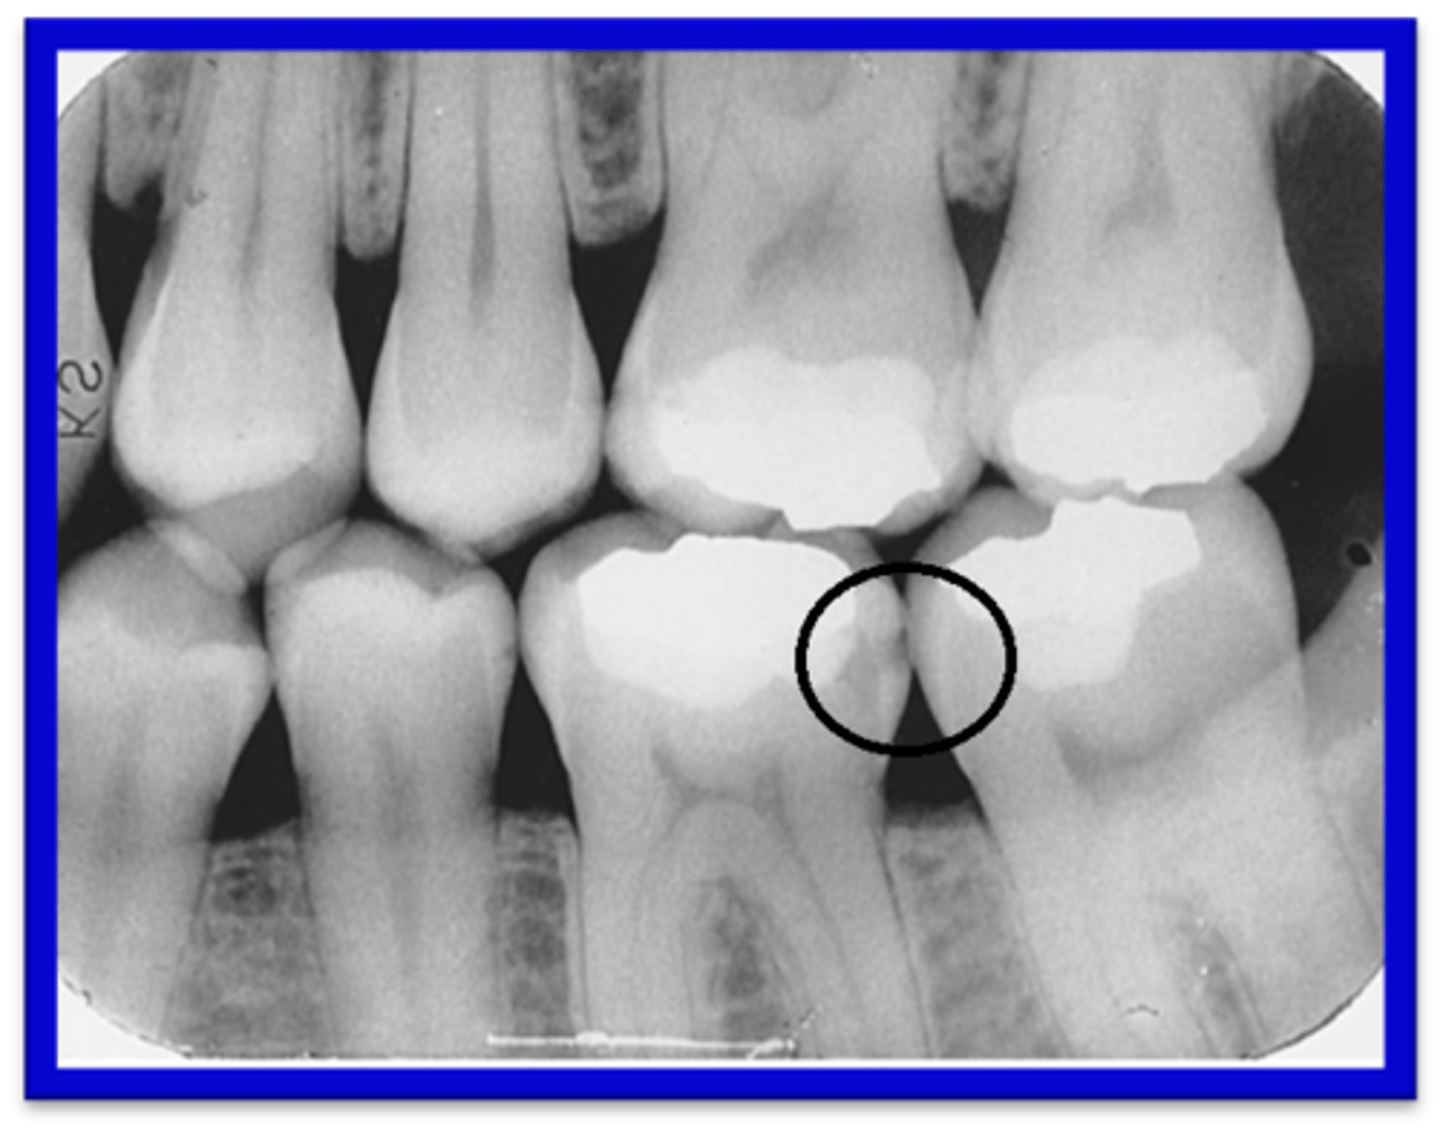

What causes overlap of interproximal spaces on an image?

Incorrect horizontal angulation.